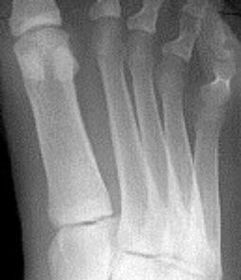

Describe the alignment of metatarsal 2 | There is no angulation nor displacement of the distal segment relative to the proximal segment. |

Describe the alignment of metatarsal 3 | The distal segment is displaced laterally (50% apposition) and angulated medially. |

Describe the alignment of metatarsal 4 | The distal segment is displaced laterally (75% apposition) but there is no apparent angulation. |

Describe the tubulation of the metatarsals | Metatarsals are overtubulated - decreased girth. |

Describe the tubulation of the metatarsals | Metatarsals are undertubulated - increased girth. |